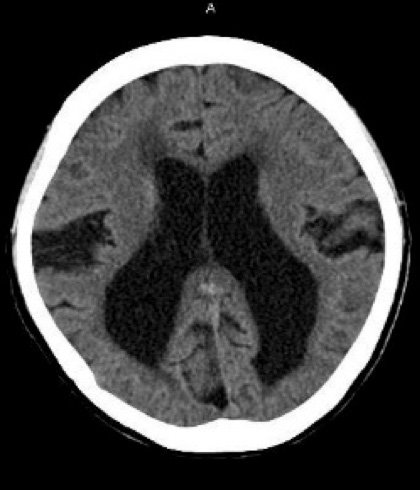

脳脊髄液が異常に溜まり、脳が圧迫されることにより起こる病気です。記憶障害、歩行障害(歩行が遅くなる)、尿失禁が症状として現れます。